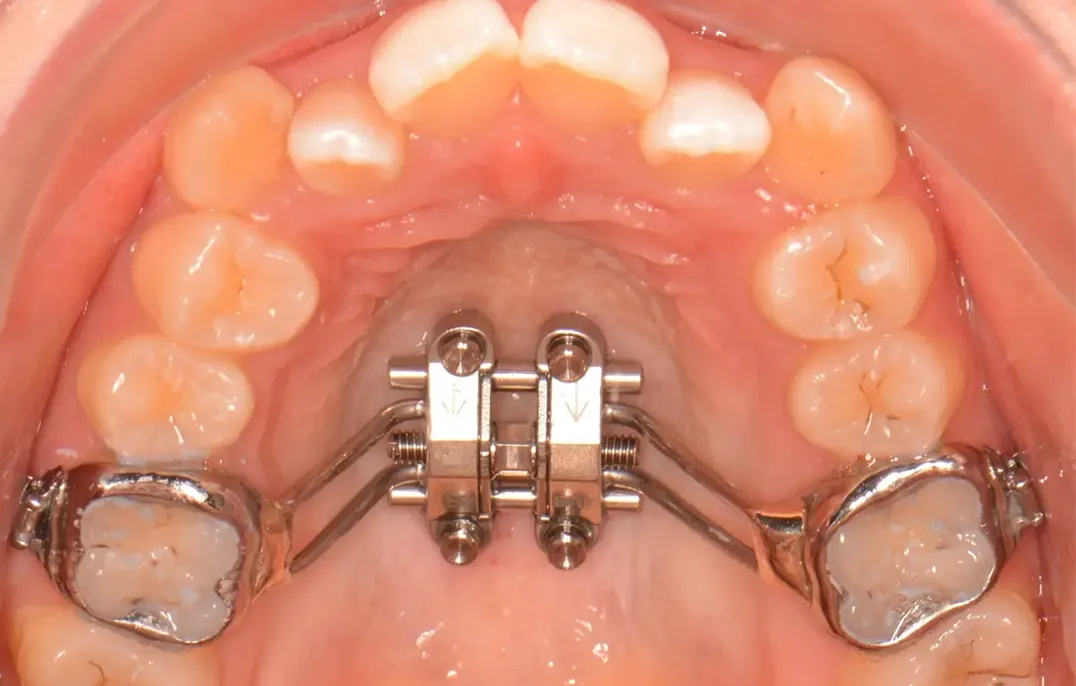

口蓋正中に埋入したアンカースクリュー

パラタル・レバー・アーム・システム

(PLAS)

SHU_lider